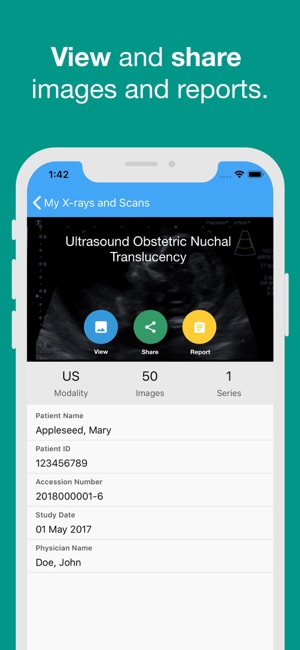

RadLink Patient Portal manages your personal radiology records with 24/7 secure online access from any computer, smartphone or tablet. This means when you visit an imaging centre that is under RadLink, you will be able to receive a permanent, digital copy of your imaging record and share easily with any healthcare professional. RadLink Patient Portal will help you to take a more active, informed role in managing your healthcare needs.